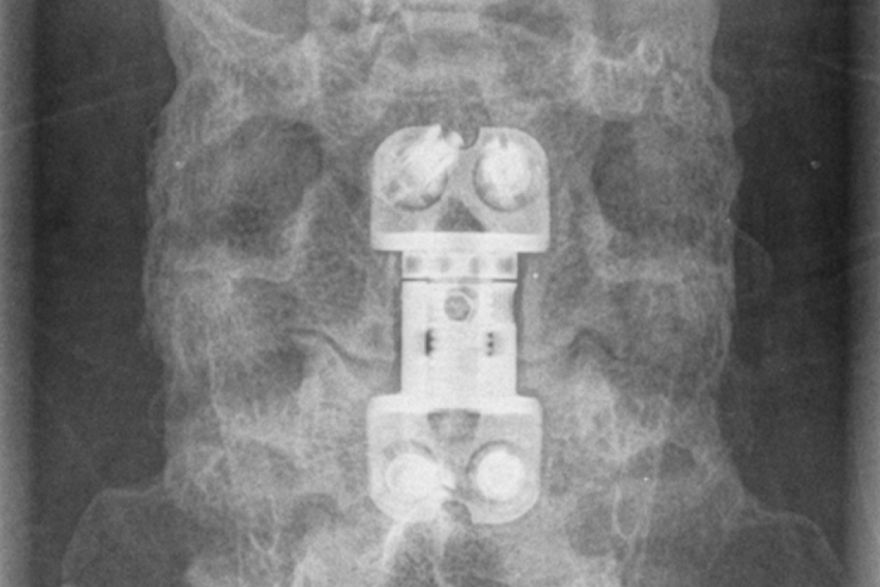

Halswirbelquerschnitt mit 18 Jahren!

Infolge eines schweren Unfalls im Dezember 2007 war die Diagnose niederschmetternd. Das stellte Sebastians Leben zunächst einmal vollkommen auf den Kopf. Von einem auf den anderen Tag konnte Sebastian fast 95% seiner Muskeln nicht mehr bewegen. Nicht nur seine Beine, sondern auch ein Großteil seiner Arme und Hände sind gelähmt. Sebastian war zu diesem Zeitpunkt 24 Stunden pro Tag auf Hilfe angewiesen.